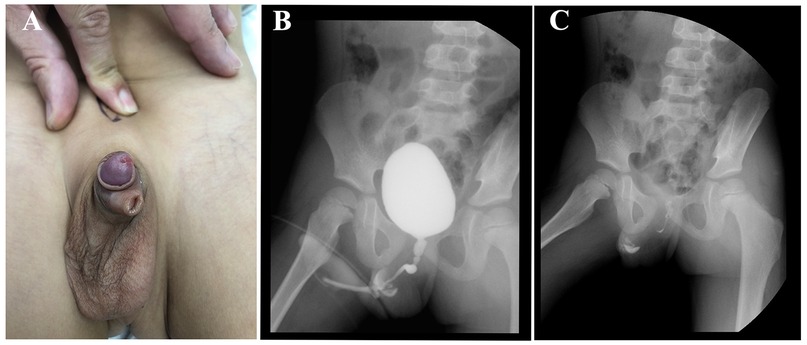

Background: Pediatric penile hamartoma is extremely rare. Preoperative imaging often cannot definitively characterize the lesion, and histopathology remains the diagnostic gold standard. We report a child with penile hamartoma and torsion, discuss management, and compare outcomes with the literature. Methods: We retrospectively analyzed the clinical presentation, imaging, intraoperative findings, and pathology. Relevant reports were reviewed for comparison. Results: Complete excision of a ventral hamartomatous appendage plus circumcision and release of a fibrous tethering band achieved immediate torsion correction in a single stage. Histopathology showed stratified squamous epithelium with proliferative fibrous and adipose tissue containing nerve bundles, ganglion cells, and focal smooth muscle— consistent with hamartoma. Recovery was uneventful; at 12 months no recurrence was observed. Conclusion: Etiology‑targeted, one‑stage correction—degloving (circumcision), release of tethering bands, complete lesion excision, and simultaneous torsion repair—can be safe and effective. Long‑term follow‑up is advised.